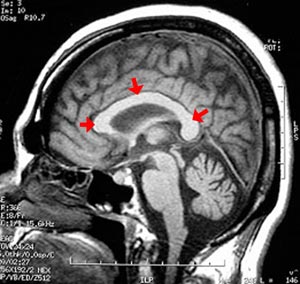

Figura 100 - Ressonância nuclear magnética do encéfalo (normal) antes da cirurgia.

Figura 102 - Ressonância nuclear magnética do encéfalo depois da cirurgia demonstrando a interrupção de 2/3 anteriores do corpo caloso (setas azuis)